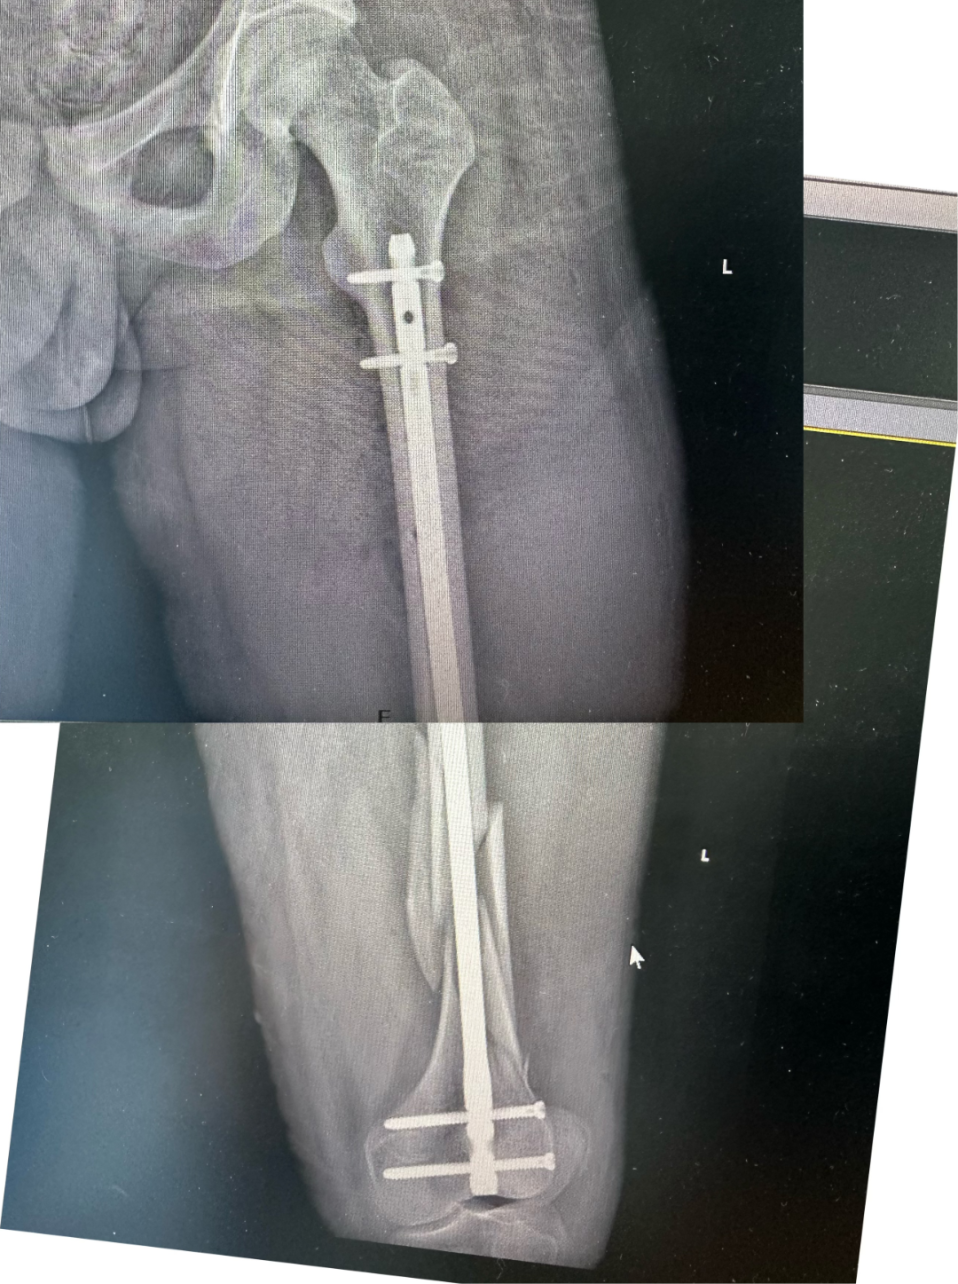

术后,ICU 团队 24 小时值守,密切监测循环、呼吸及肢体血运,精准调控抗凝、抗休克抗及营养支持方案,为患者平稳度过危险期提供了坚实保障。2 月 24 日,待病情稳定后,患者顺利接受了「左股骨粉碎性骨折闭合复位髓内钉内固定术」。

目前,患者恢复良好,生命体征平稳,肢体血运及功能逐步改善,近期即可顺利出院。家属含泪感激:「是医院的全力救治,给了我家人第二次生命。」